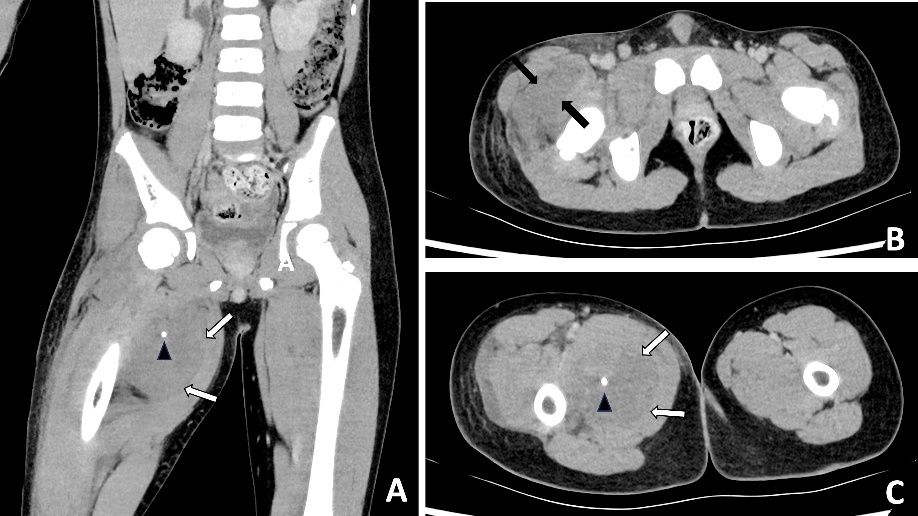

A previously well 47-year-old male presented to the emergency department with worsening atraumatic right shoulder pain and malaise. He was septic with a white blood cell count of 13.4 × 109/L and C-reactive protein of 489 mg/L. A chest CT reported a ‘large ill-defined heterogeneous density mass lesion within the upper medial posterior chest…with small volume fluid and subcutaneous fat stranding’. Internal hyperdense foci were interpreted as calcification or possible foreign bodies (Figure 3). The patient was admitted to the Intensive Care Unit (ICU) and placed on vasopressors support. The plastic surgery team was consulted to provide an opinion on urgent surgical management.

In retrospect, the presence of intramuscular phleboliths on CT in the cases presented above was the best clue to the diagnosis of an infected VM. Phleboliths occur in approximately 30 per cent of VMs.15 Intramuscular phleboliths have a limited imaging differential diagnosis and are generally taken to be pathognomic of VM.16 Radiologist and clinician awareness of this rare presentation of VMs is important; if intramuscular phleboliths are identified, the diagnosis of VM should be raised and the use of MRI may further assist in the diagnosis. If clinical doubt remains in an acutely unwell patient, prompt surgery to exclude necrotising soft tissue infection is prudent.

Timely surgical exploration is indicated in septic patients where necrotising soft tissue infection cannot be excluded. However, it is important to consider rare conditions that may present similarly, such as infected VMs. The presence of intramuscular phleboliths on CT, especially in a child, is the best imaging clue to this unusual diagnosis and should not be overlooked.